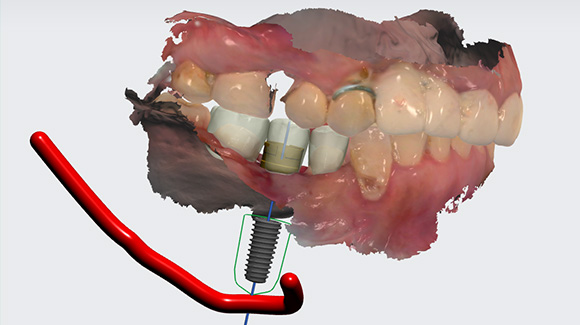

네비게이션 가이드 자체 제작

수술을 집도하시는 원장님께서 직접 임플란트 식립

위치를

디자인하셔서 훨씬 더 정확합니다.

원내에서 가이드를 자체제작하여 비용을 절감하고,

빠른

시일내로 제작이 가능하여 시간도 절감시켜드리고 있습니다.